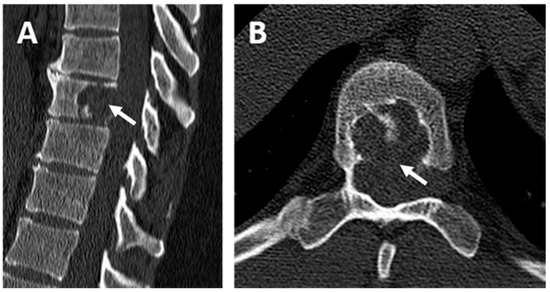

2. Case Report